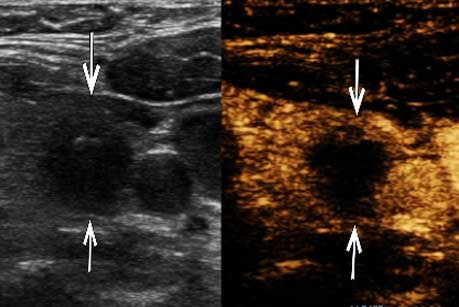

甲状腺左叶实性结节,形态欠不规则,边界尚清,局部紧邻后方被膜,结节内部可见强回声钙

超声造影全程结节无增强